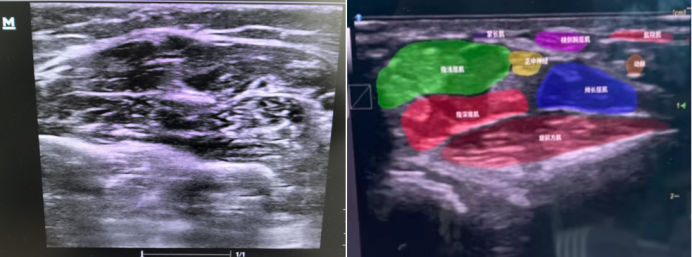

2.1  病情判定与组织分割

AI辅助判定病情场景中,结合图1可见:绿色方框标注位置,AI识别判定为存在异常表现;黄色方框标注区域,AI提示该部位需重点关注;红色方框标注处,AI建议在此位置优先开展核心诊断,为临床病情判定提供指向性参考 ,辅助医护人员更高效地识别关键病情信息。

1  AI辅助判断病情

在组织分割中,AI可自动标注超声图像中的精细结构。图2左为左前臂普通超声图像,因结构显示缺乏直观标识,难以直接分辨具体解剖部位。借助AI超声技术处理后,呈现为图2右所示图像,AI可对肌肉、神经、血管等不同解剖结构进行精准标识区分。这种AI辅助超声的模式,在未来肌肉、脏器相关检查及穿刺操作等场景中(图3),有望为临床提供更清晰、直观且具精准解剖指引的超声成像表现,助力提升诊疗操作的准确性与效率。

2  AI辅助判断组织分割